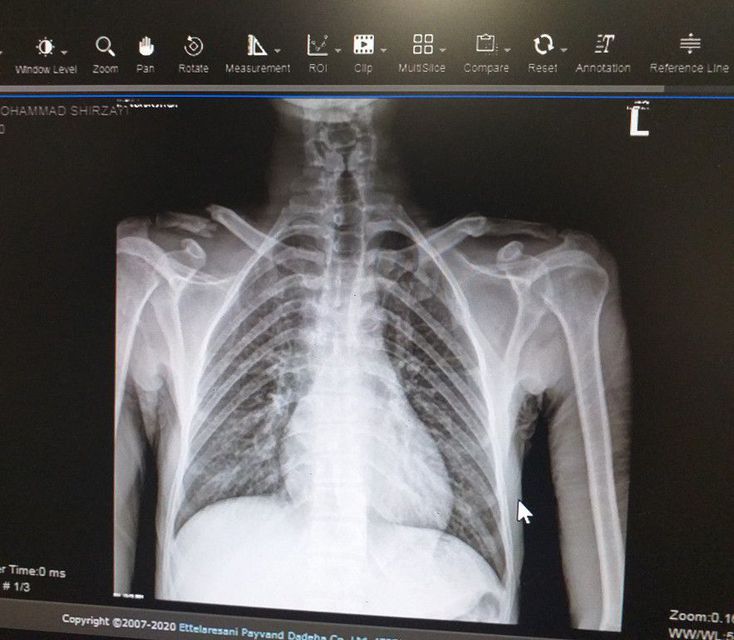

What is your diagnosis?

Right distal clavicle complete fracture.

Trachea not in line, clavicle fracture definitely noted

The fracture of clavicle is clear ...what about stenosis on trachea ?

Complete right clavicula fracture

Right distal clavicula fracture and croup

Right clavicle fracture!